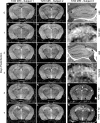

Many viruses, including picornaviruses, have the potential to infect the central nervous system (CNS) and stimulate a neuroinflammatory immune response, especially in infants and young children. Cognitive deficits associated with CNS picornavirus infection result from injury and death of neurons that may occur due to direct viral infection or during the immune responses to virus in the brain. Previous studies have concluded that apoptosis of hippocampal neurons during picornavirus infection is a cell-autonomous event triggered by direct neuronal infection. However, these studies assessed neuron death at time points late in infection and during infections that lead to either death of the host or persistent viral infection. In contrast, many neurovirulent picornavirus infections are acute and transient, with rapid clearance of virus from the host. We provide evidence of hippocampal pathology in mice acutely infected with the Theiler's murine encephalomyelitis picornavirus. We found that CA1 pyramidal neurons exhibited several hallmarks of apoptotic death, including caspase-3 activation, DNA fragmentation, and chromatin condensation within 72 hours of infection. Critically, we also found that many of the CA1 pyramidal neurons undergoing apoptosis were not infected with virus, indicating that neuronal cell death during acute picornavirus infection of the CNS occurs in a non-cell-autonomous manner. These observations suggest that therapeutic strategies other than antiviral interventions may be useful for neuroprotection during acute CNS picornavirus infection.